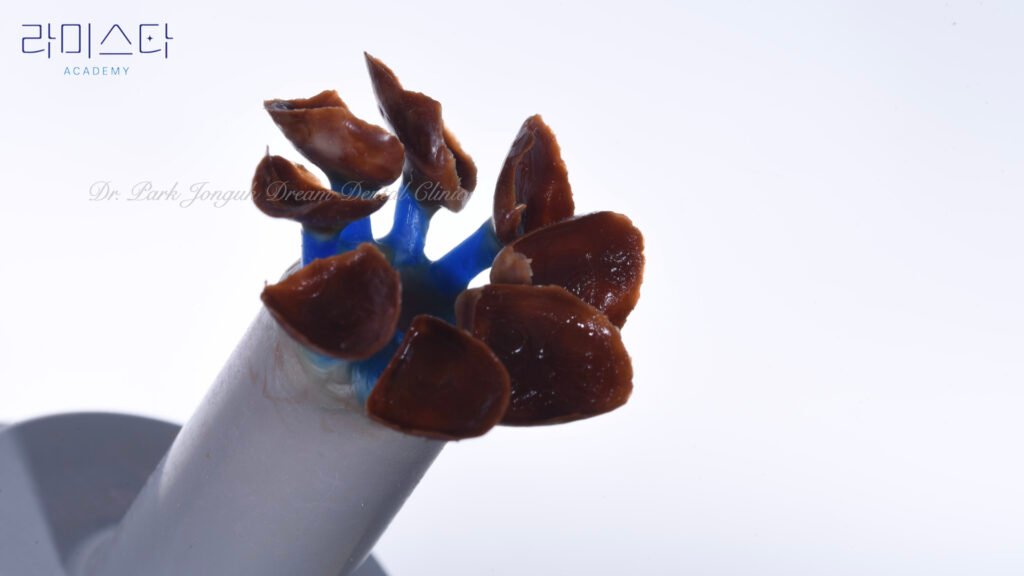

사진 5-13은 **핸드메이드 방식의 라미네이트 제작 과정(Hand-layered laminate fabrication process)**입니다. 완전히 다른 차원의 접근입니다.

1단계: 세라믹 베이스 제작

코어 구조(Core structure) 형성: 기본 골격이 되는 세라믹 베이스를 제작합니다. 치아의 기본 형태, 크기, 두께를 확립합니다.

2단계: 다층 빌드업

“그 위에 빌드업을 통해서 세라믹을 축성해 나갑니다.”

단계적 적층(Sequential layering): 한 층씩 세라믹 파우더를 정성스럽게 쌓아 올립니다. 각 층마다 소성(Firing, 고온 가열)을 거쳐 응결시킵니다.

3단계: 부위별 맞춤 세라믹 적용

핵심 원리: “치아의 부위별 색감과 투명감을 각기 다른 세라믹을 이용해서 만들어야 합니다.”

자연치아는 균일하지 않습니다. 부위마다 색조, 명도, 채도, 투명도가 다릅니다. 이를 재현하려면:

치경부(Cervical area): 불투명하고 따뜻한 상아색(Warm ivory) 세라믹. 덴틴층 재현.

중간부(Body area): 반투명하고 밝은 에나멜 색 세라믹. 법랑질 색조 재현.

절단연(Incisal edge): 투명 세라믹(Translucent ceramic). 자연스러운 빛 투과.

표면 특성화층(Surface characterization): 미세 텍스처, 백색반점(White spot), 발육엽(Developmental lobe) 등 개별 특성 표현.

각기 다른 여러 종류의 세라믹을 사용하여 자연치아의 복잡한 다층 구조와 광학 특성을 정밀하게 재현합니다.